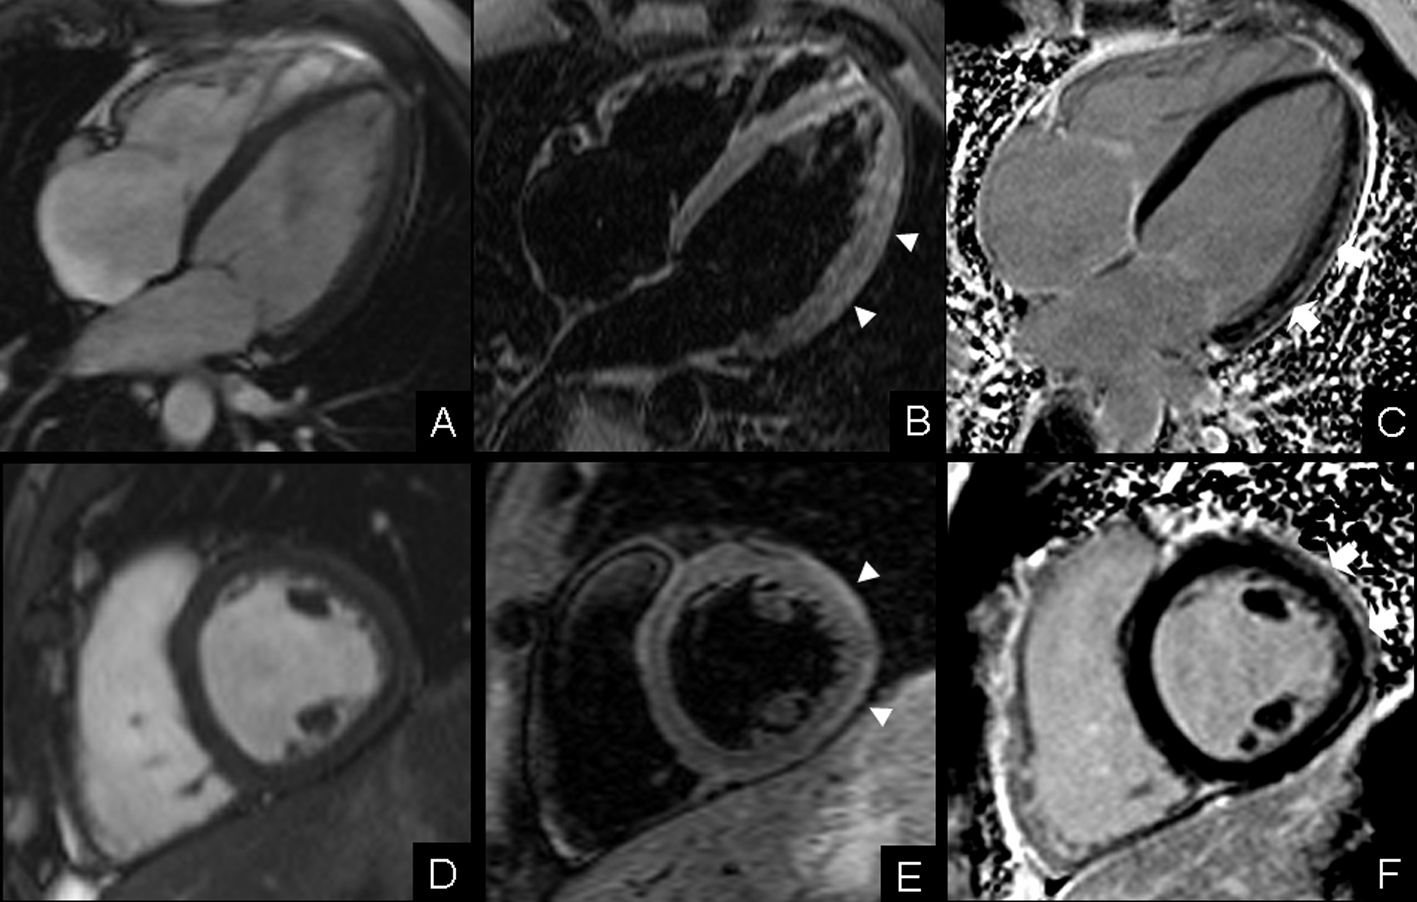

Las miocardiopatías son una causa frecuente de morbimortalidad. Entre las miocardiopatías específicas se incluye la miocarditis, una entidad que con frecuencia se presenta con manifestaciones clínicas inespecíficas y puede resultar de difícil diagnóstico o incluso pasar desapercibida. El éxito de las técnicas tradicionalmente empleadas para el diagnóstico de miocarditis, incluyendo la biopsia endomiocárdica, es limitado. Tras su implantación en la práctica clínica, la resonancia magnética (RM) cardiaca se ha convertido en la mejor técnica diagnóstica no invasiva disponible para el diagnóstico de miocarditis aguda.Descargas